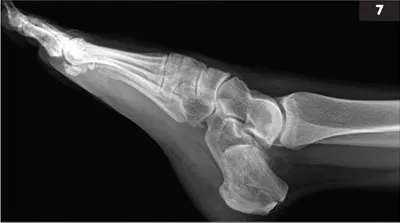

7 A 43-year-old female fell off a ladder and had severe pain in her left heel.

i. What does this radiograph demonstrate (7)?

ii. Is surgery necessary?